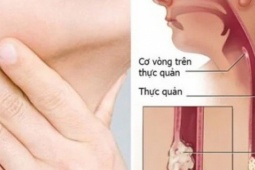

Trang Ettoday đưa tin, ông Zhang (59 tuổi) sống ở Đài Loan (Trung Quốc) làm việc trong ngành xây dựng. Do công việc nặng nhọc nên ông thường xuyên hút thuốc, uống rượu, nhai trầu. Theo thời gian, ông nhận thấy mình bị đau khi nuốt và bị trào ngược dạ dày thực quản.

Ban đầu, ông Zhang dùng thuốc giảm đau hoặc thuốc không kê đơn, các triệu chứng thuyên giảm đôi chút. Tuy nhiên, gần đây ông tiếp tục gặp khó khăn khi nuốt, sụt cân không rõ nguyên nhân, thậm chí cả bánh pudding mềm cũng không thể nuốt. Khi nhập viện cấp cứu, ông được chẩn đoán mắc bệnh ung thư thực quản giai đoạn 3 với di căn bạch huyết.

Bác sĩ Liao Qiyao nhắc nhở rằng, có nhiều yếu tố gây ra ung thư thực quản. Những người có thói quen xấu như hút thuốc, uống rượu, nhai trầu hoặc thường có các triệu chứng bất thường như trào ngược dạ dày đều có nguy cơ mắc ung thư cao.

Bác sĩ Liao Qiyao cho rằng, phẫu thuật là phương pháp điều trị khả thi đối với bệnh ung thư thực quản giai đoạn đầu. Đối với những bệnh nhân đã tiến triển, nếu phát hiện di căn bạch huyết thì nên sử dụng hóa trị và xạ trị trước, khi khối u thu nhỏ lại sẽ phẫu thuật.

Nếu ung thư thực quản đã xâm lấn ra ngoài thành thực quản hoặc đã di căn rộng, hóa trị và xạ trị dứt điểm là phương pháp điều trị chính.

Nhìn chung, phẫu thuật kết hợp với hóa trị và xạ trị là lựa chọn tốt nhất để kiểm soát hiệu quả ung thư thực quản giai đoạn muộn.